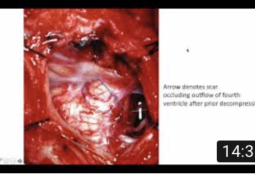

Recurrent Syringomyelia After Chiari Decompression Surgery

Obex Exploration & Duraplasty to Improve Syrinx Resolution Following Chiari Decompression